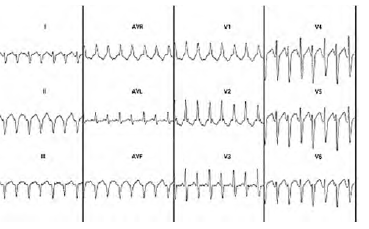

Uma paciente de 50 anos de idade chega no pronto-socorro com intensa palpitação, mal-estar e sudorese. É então solicitado um ECG, demonstrado na imagem.

Com relação a esse eletrocardiograma e com base nos conhecimentos correlatos, assinale a alternativa que indica o primeiro medicamento a ser administrado no plantão.